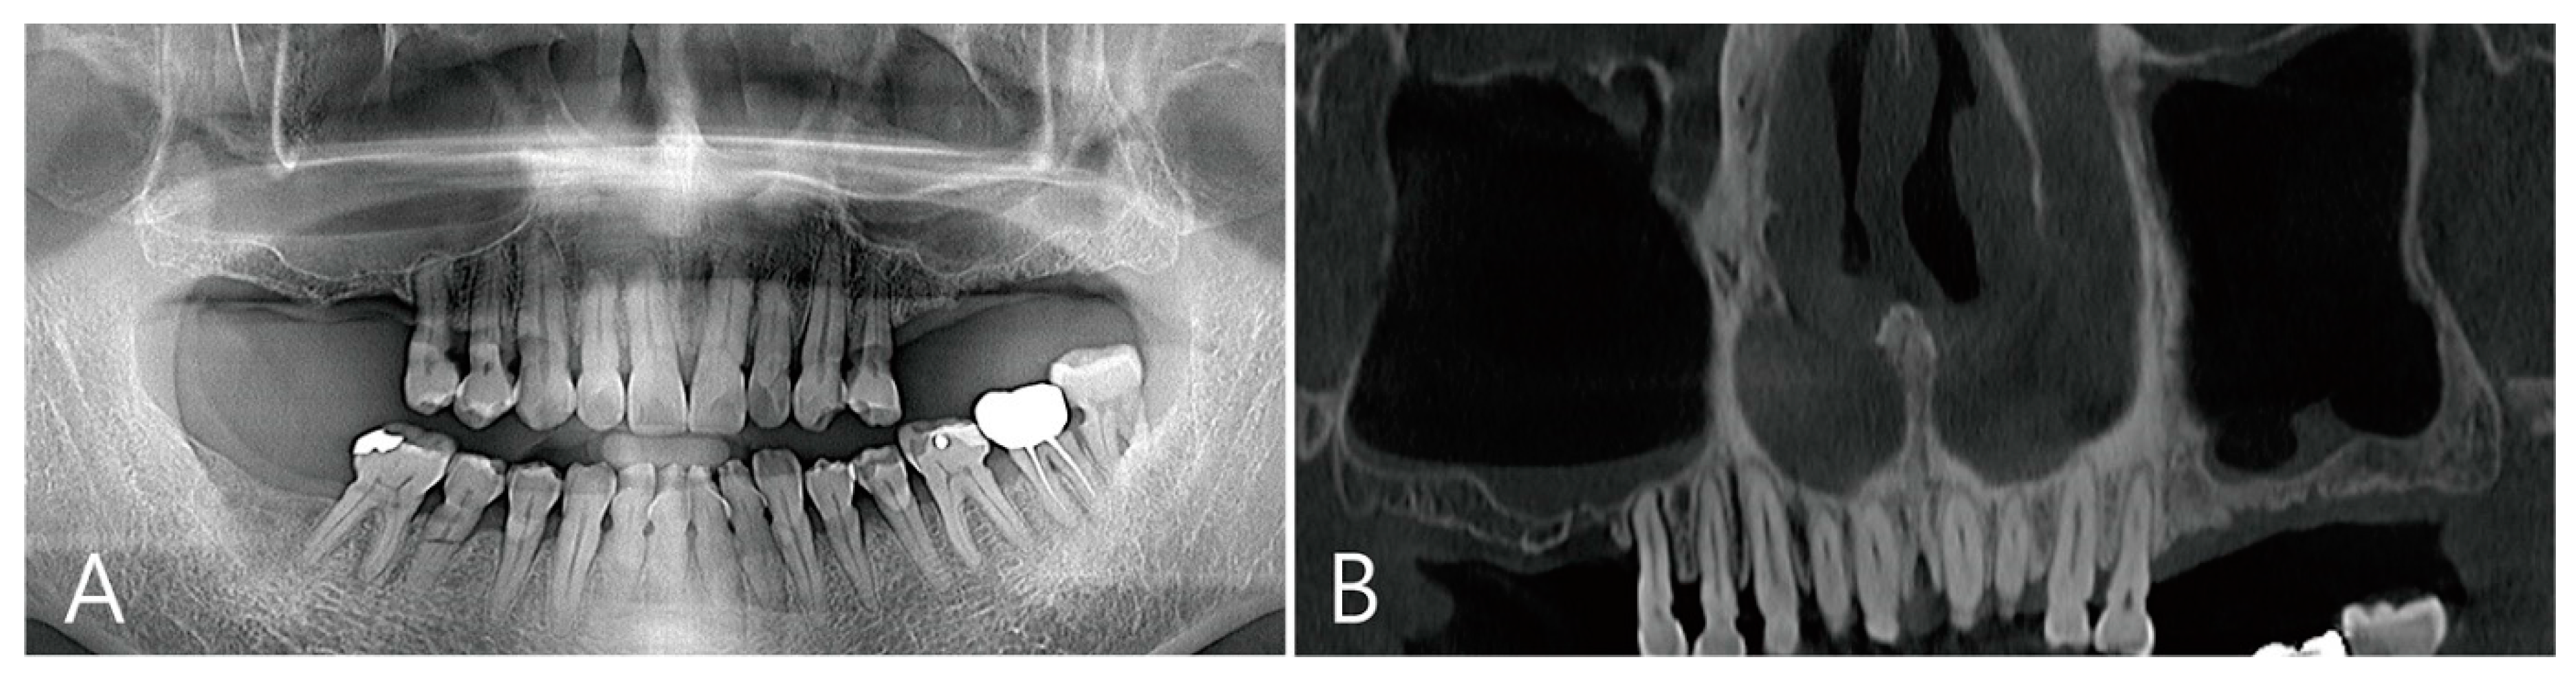

Patient 2 is a 72-year-old female non-smoker with hypertension who had been taking antihypertensive drugs for a long time (Table 1). This patient visited the clinic for implant placement of the maxillary left and right posterior teeth. Preoperative panoramic radiography and CBCT were taken. There were also severely atrophied residual ridges and pneumatized maxillary sinuses of the edentulous ridges in the maxillary posterior regions (Figure 4A). There was no thickening of the sinus membrane as a panoramic image of the preoperative CBCT (Figure 4B). A lateral bone window was prepared using the lateral window technique. There was no perforation of the maxillary sinus mucosa during the sinus floor elevation process. Three osteotomy sites were prepared for implant placement (Figure 5A). The elevated sinus cavity was filled with xenograft (A-Oss, Osstem, Seoul, Korea) and the removed lateral window bone was repositioned. Three implants (Ø 4.3 × 10, Implantium, Dentium, Suwon, Korea) were placed (Table 1). The flap was closed without a barrier membrane covering (Figure 5B). There were no complications during the healing process and no adverse events. Recovery was performed 6 months after surgery. The repositioned lateral window site was well fused to the surrounding native bone (Figure 5C). To remove the large grafting void, the repositioned lateral window also had to be removed. The removed specimen (1.5 × 1.2 cm) appeared shiny on the inner surface and was lined with soft tissue (Figure 5D). In the area where the grafting void was removed, some of the maxillary sinus mucosae were also removed and perforation occurred (Figure 5E). The perforated mucosa was covered with a resorbable collagen membrane (Genoss, Suwon, Korea) and then filled with bone graft material (Osteon III, Genoss, Suwon, Korea). After the healing abutment was inserted, the flap was closed (Figure 5F).

Figure 4. Case 2. (A) On preoperative panoramic radiography, severely atrophied residual ridges were observed in the missing area of the left and right maxillary molars, and the maxillary sinuses were pneumatized; (B) a panoramic image of the preoperative CBCT showed slight thickening of the sinus membrane on the sinus floor.